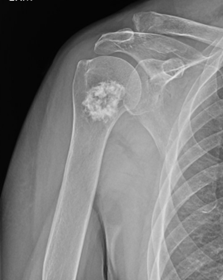

Ακτινογραφίες . Οι βλάβες του χόνδρου μπορούν συχνά να αναγνωριστούν από την ακτινογραφική τους εμφάνιση (πώς φαίνονται σε μια ακτινογραφία).

Στην ακτινογραφία:

- Τα εγχονδρώματα έχουν την κλασική εμφάνιση λευκών ασβεστώσεων τύπου «ποπ κορν» χωρίς επιθετικά χαρακτηριστικά που θα μπορούσαν να αλλάξουν ή να βλάψουν το περιβάλλον οστό.

Καλοήθης όγκος χόνδρου με μεγαλύτερη συνάφεια με εγχόνδρωμα.